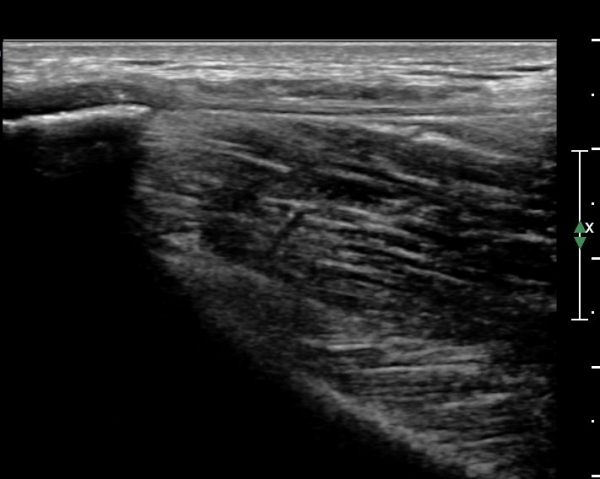

°í°üÀý ¿ÜÃø, ¹Ù·Î µÚ Á¾´Ü¸é°Ë»ç¿Í Ⱦ´Ü¸é °Ë»ç»ó °üÀý ¿Í¼øºÎÀ§¿¡ Ä¿´Ù¶õ °í¿¡ÄÚ ¼®È¸È­°¡ °üÂûµÊ(»çÁø 8, 9)